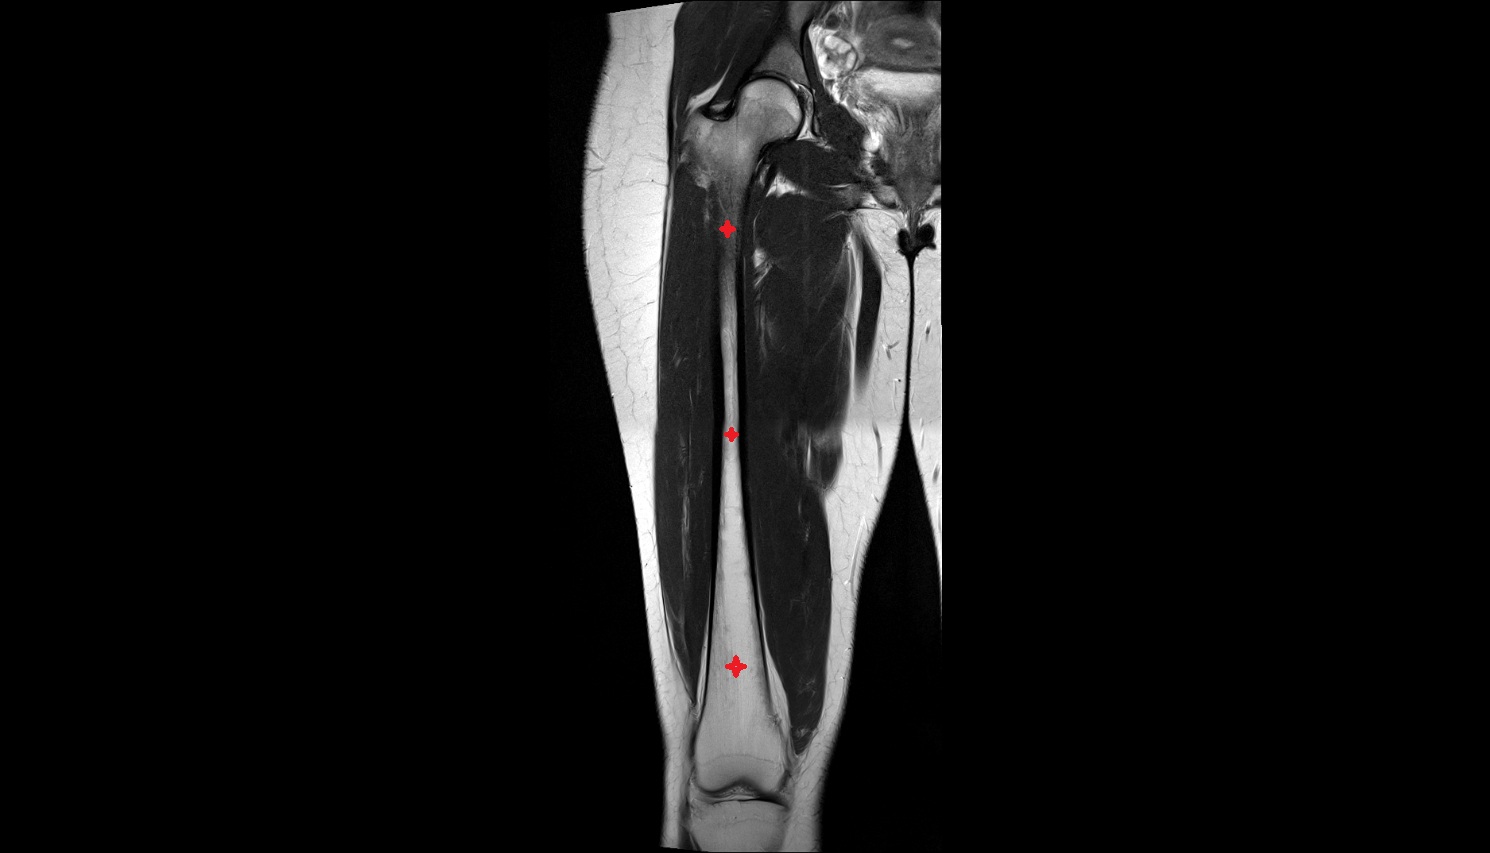

- Femur

- Femoral shaft

- Body of femur

- Semitendinosus muscle

- Semimembranosus muscle

- Biceps femoris muscle (Long head)

- Biceps femoris muscle (Short head)

- Vastus intermedius muscle

- Vastus lateralis muscle

- Vastus medialis muscle